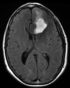

The most common task in Diffusion MRI registration is aligning an anatomical reference with the tensor data or fiber-tracts derived from DTI. Because the DTI is tensor data, applying a spatial transform to this image is not trivial. Hence a common approach is to align the anatomical reference (such as a T1 MRI) to the DTI image and thus avoid having to resample the tensor. This, however, preserves the strong distortions often present in the DTI image and makes anatomical referencing difficult.

Case 33: DTI baseline to T1, incl. pathol.